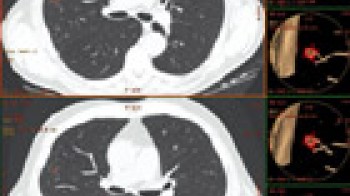

CT screening (rano otkrivanje) karcinoma pluća

Karcinom pluća je najčešći karcinom kod muškaraca,  pa se ranom otkrivanju te bolesti pridaje velika važnost. Uvođenje višeslojnog CT-a (MSCT) u kliničku praksu omogućilo je i screening (rano otkrivanje) karcinoma pluća. Pregled je namijenjen onima koji su visokog rizika za karcinom pluća i omogućava otkrivanje izrazito malih čvorova u plućima, koji mogu biti prisutni, a da nisu vidljivi na standardnom rtg snimku pluća. Rano otkrivanje ovih promjena može dramatično poboljšati uspješnost liječenja karcinoma pluća.

CT screening pluća se preporučuje uraditi pušačima starijim od 60g, a čiji pakovanje-godine index je veći od 10 (pakovanje-godine index se dobije tako što se pomnoži broj godina pušenja sa brojem kutija cigareta koje se ispuše svaki dan: preko 80% karcinoma pluća se dijagnostikuje u ljudi starijih od 60g). Drugi kandidati za pregled su pacijenti starosti 50-60g, koji imaju pakovanje-godine index 20-30 ili s drugim riziko-faktorima kao što je izlaganje azbestu ili hronična opstruktivna bolest pluća.

Šta mogu očekivati od rezultata testa?

Ako je screening CT uredan dalje ispitivanje nije potrebno.

Ako se nađe čvor u plućima, može biti potrebno uraditi detaljniji-dijagnostički CT pluća, s kontrastom. Često se za čvorove koji su nadjeni pri preventivnom pregledu ispostavi da su granulomi ili ožiljci kada se uradi detaljniji/dijagnostički CT pluca ili se radi o čvorovima benignih karakteristika, koji se potom prate u određjenim periodima da bi se bilo sigurno da se radi o zaista benignoj promjeni.